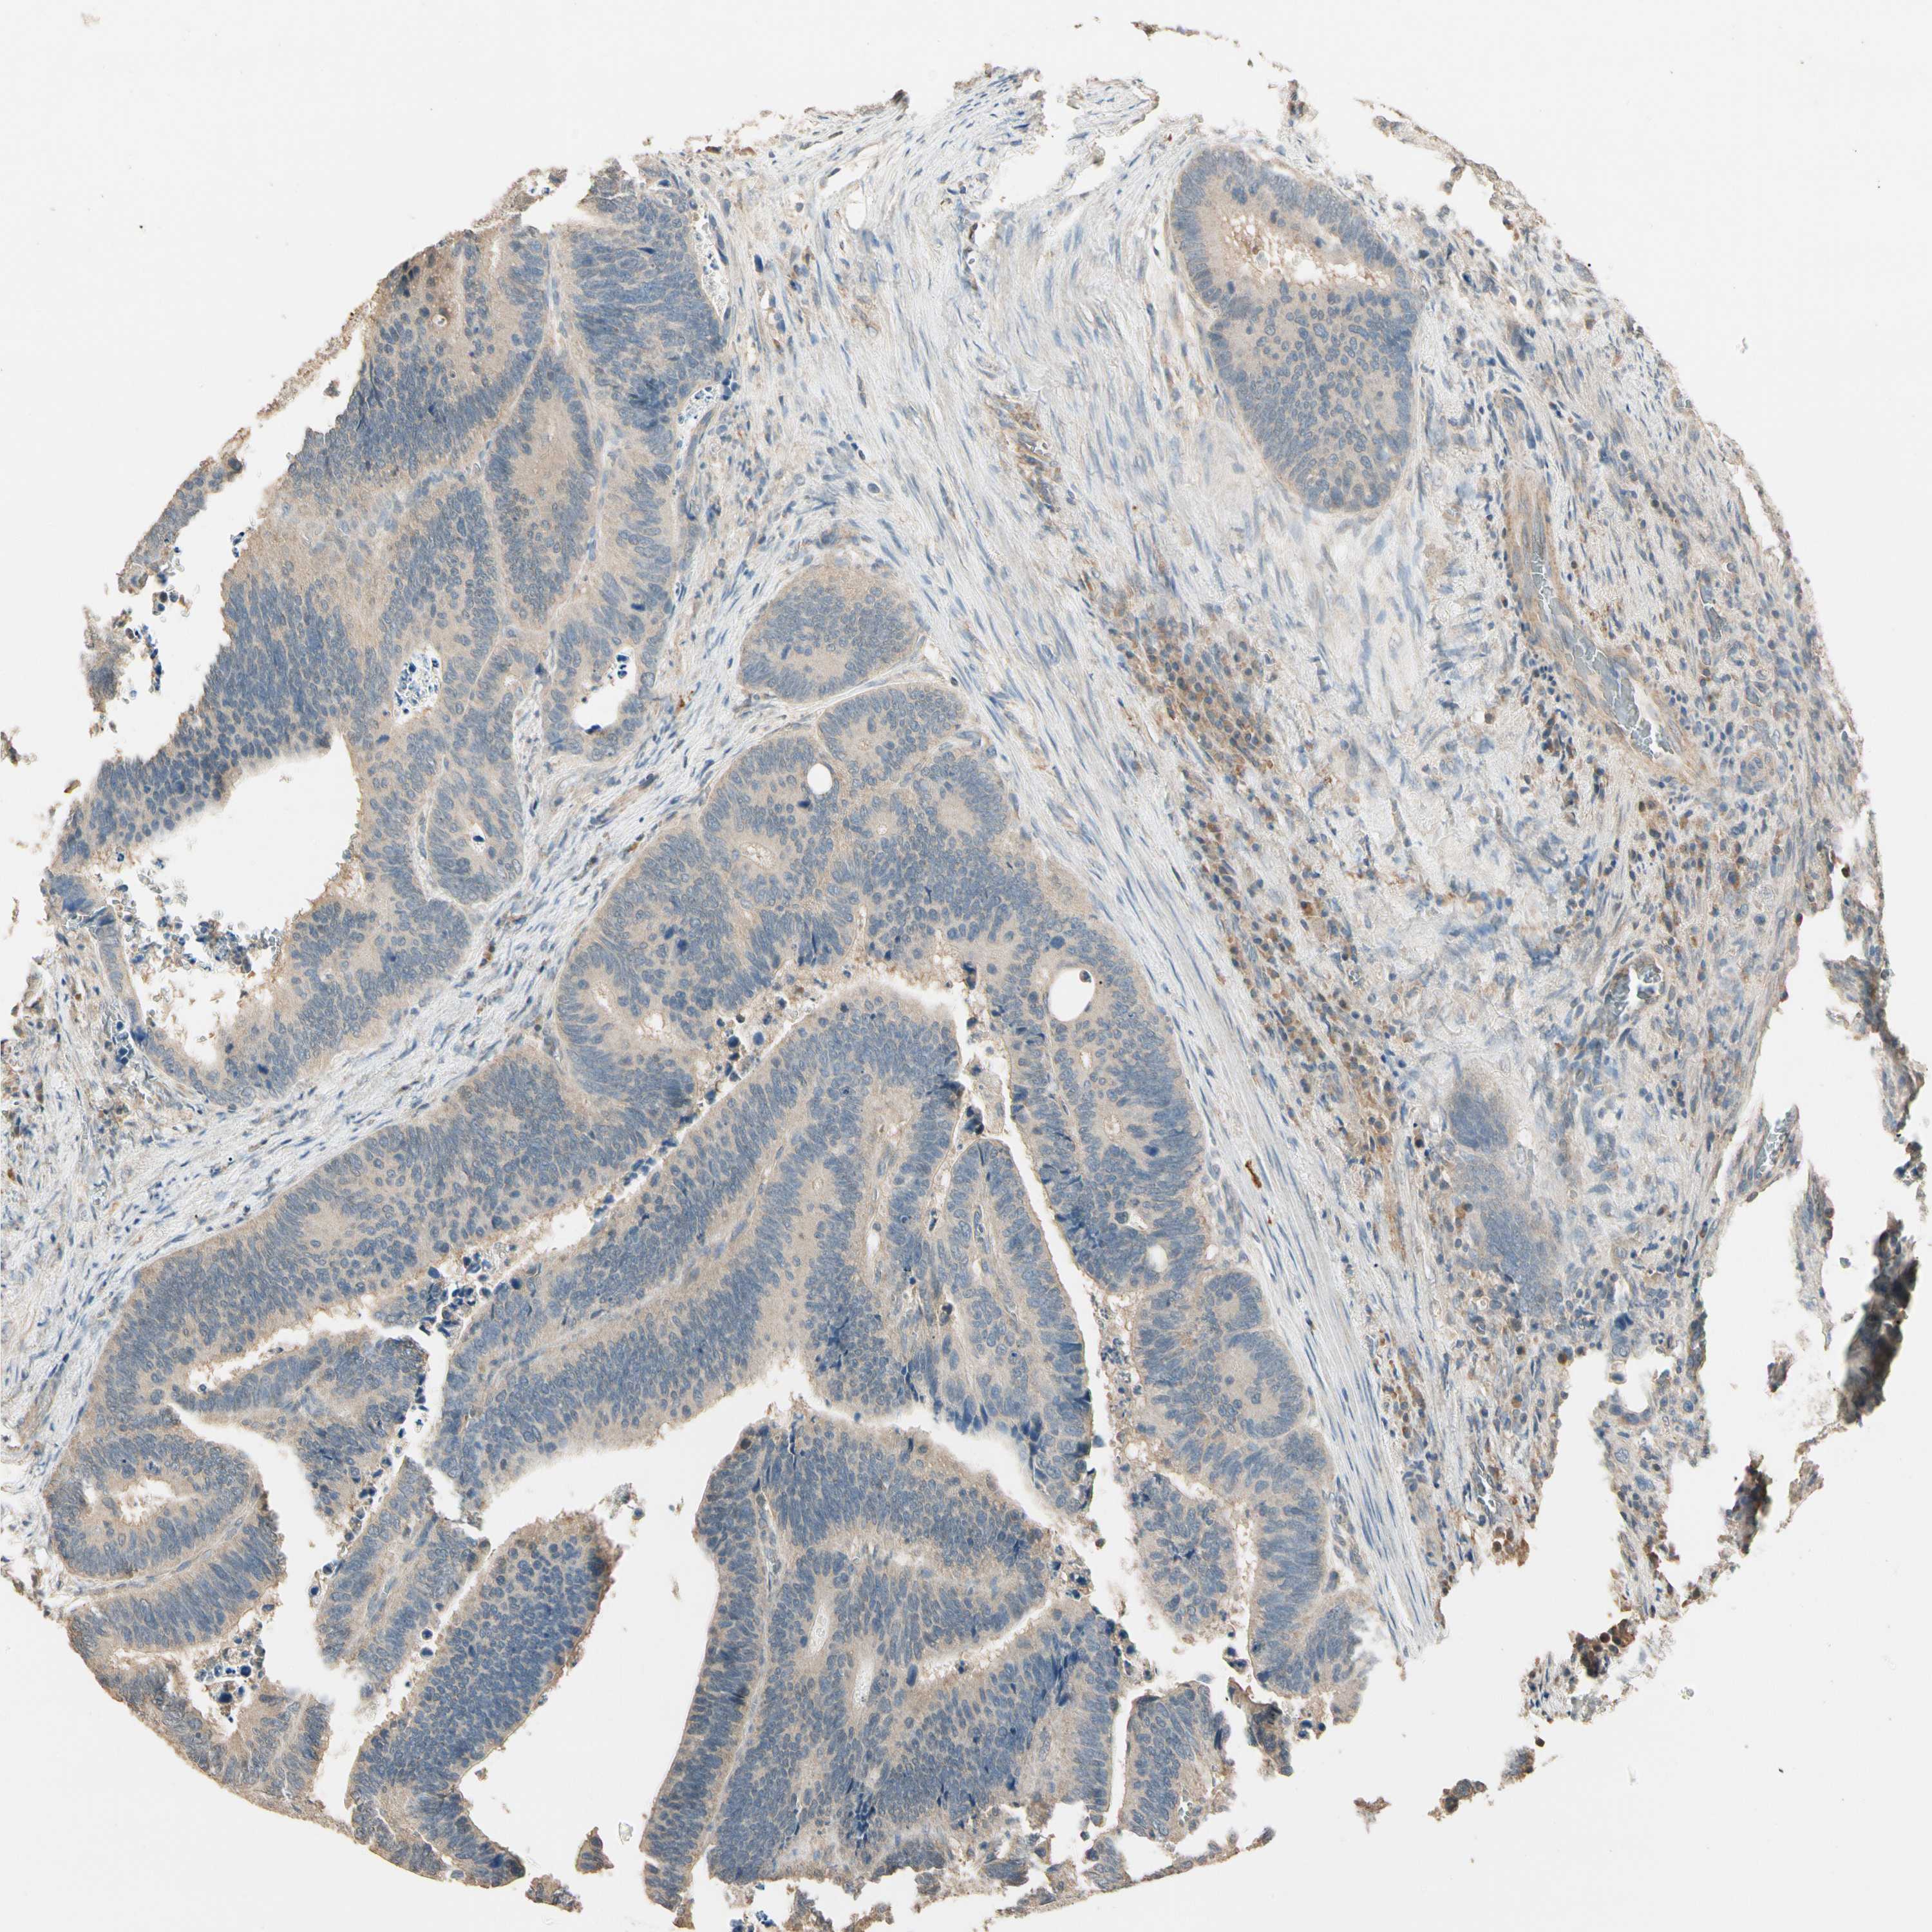

CANCER COLORECTAL CANCER Show tissue menu

Colorectal cancer

Human cancer

Colon adenocarcinoma